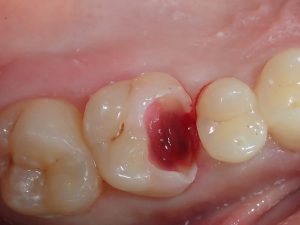

dent isolée pour  faire la Biogreffe de « BIODENTINE »

dent « biogreffée » prête à recevoir l’inla